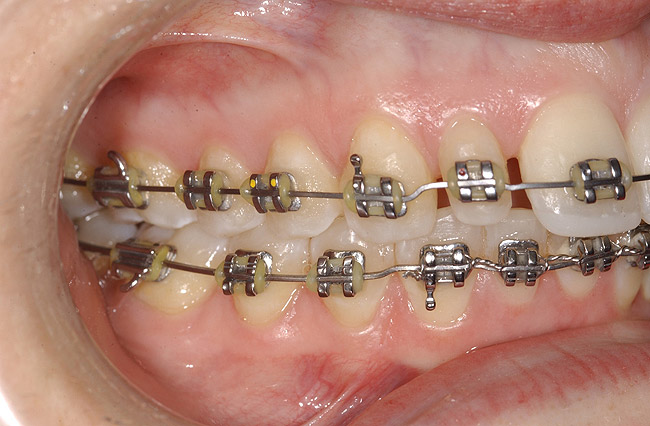

Figure 9: Orthodontic distraction osteogenesis to develop the implant site of tooth No. 23.

Figure 9

Figure 10  Radiograph of orthodontic distraction osteogenesis.

Figure 10

Figure 11  Radiograph showing developed implant site of tooth No. 23.

Figure 11